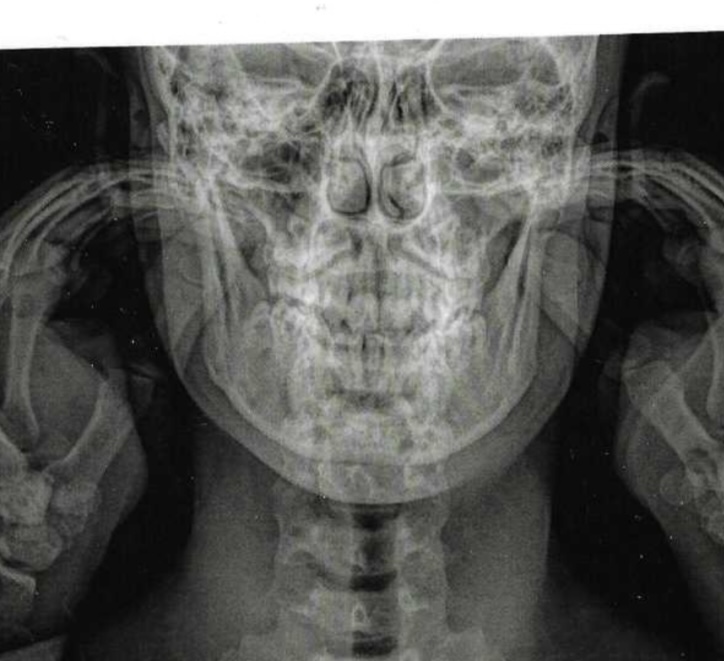

So as I said i’ve been softmaxxing for 2 years now i’m 18 and think It might be over. I think of doing a BSSO to fix my mandibular rotation and slight overbite but that’s gonna take a long time. I need someone the tell if there is anything left so I can start slaying ltbs.